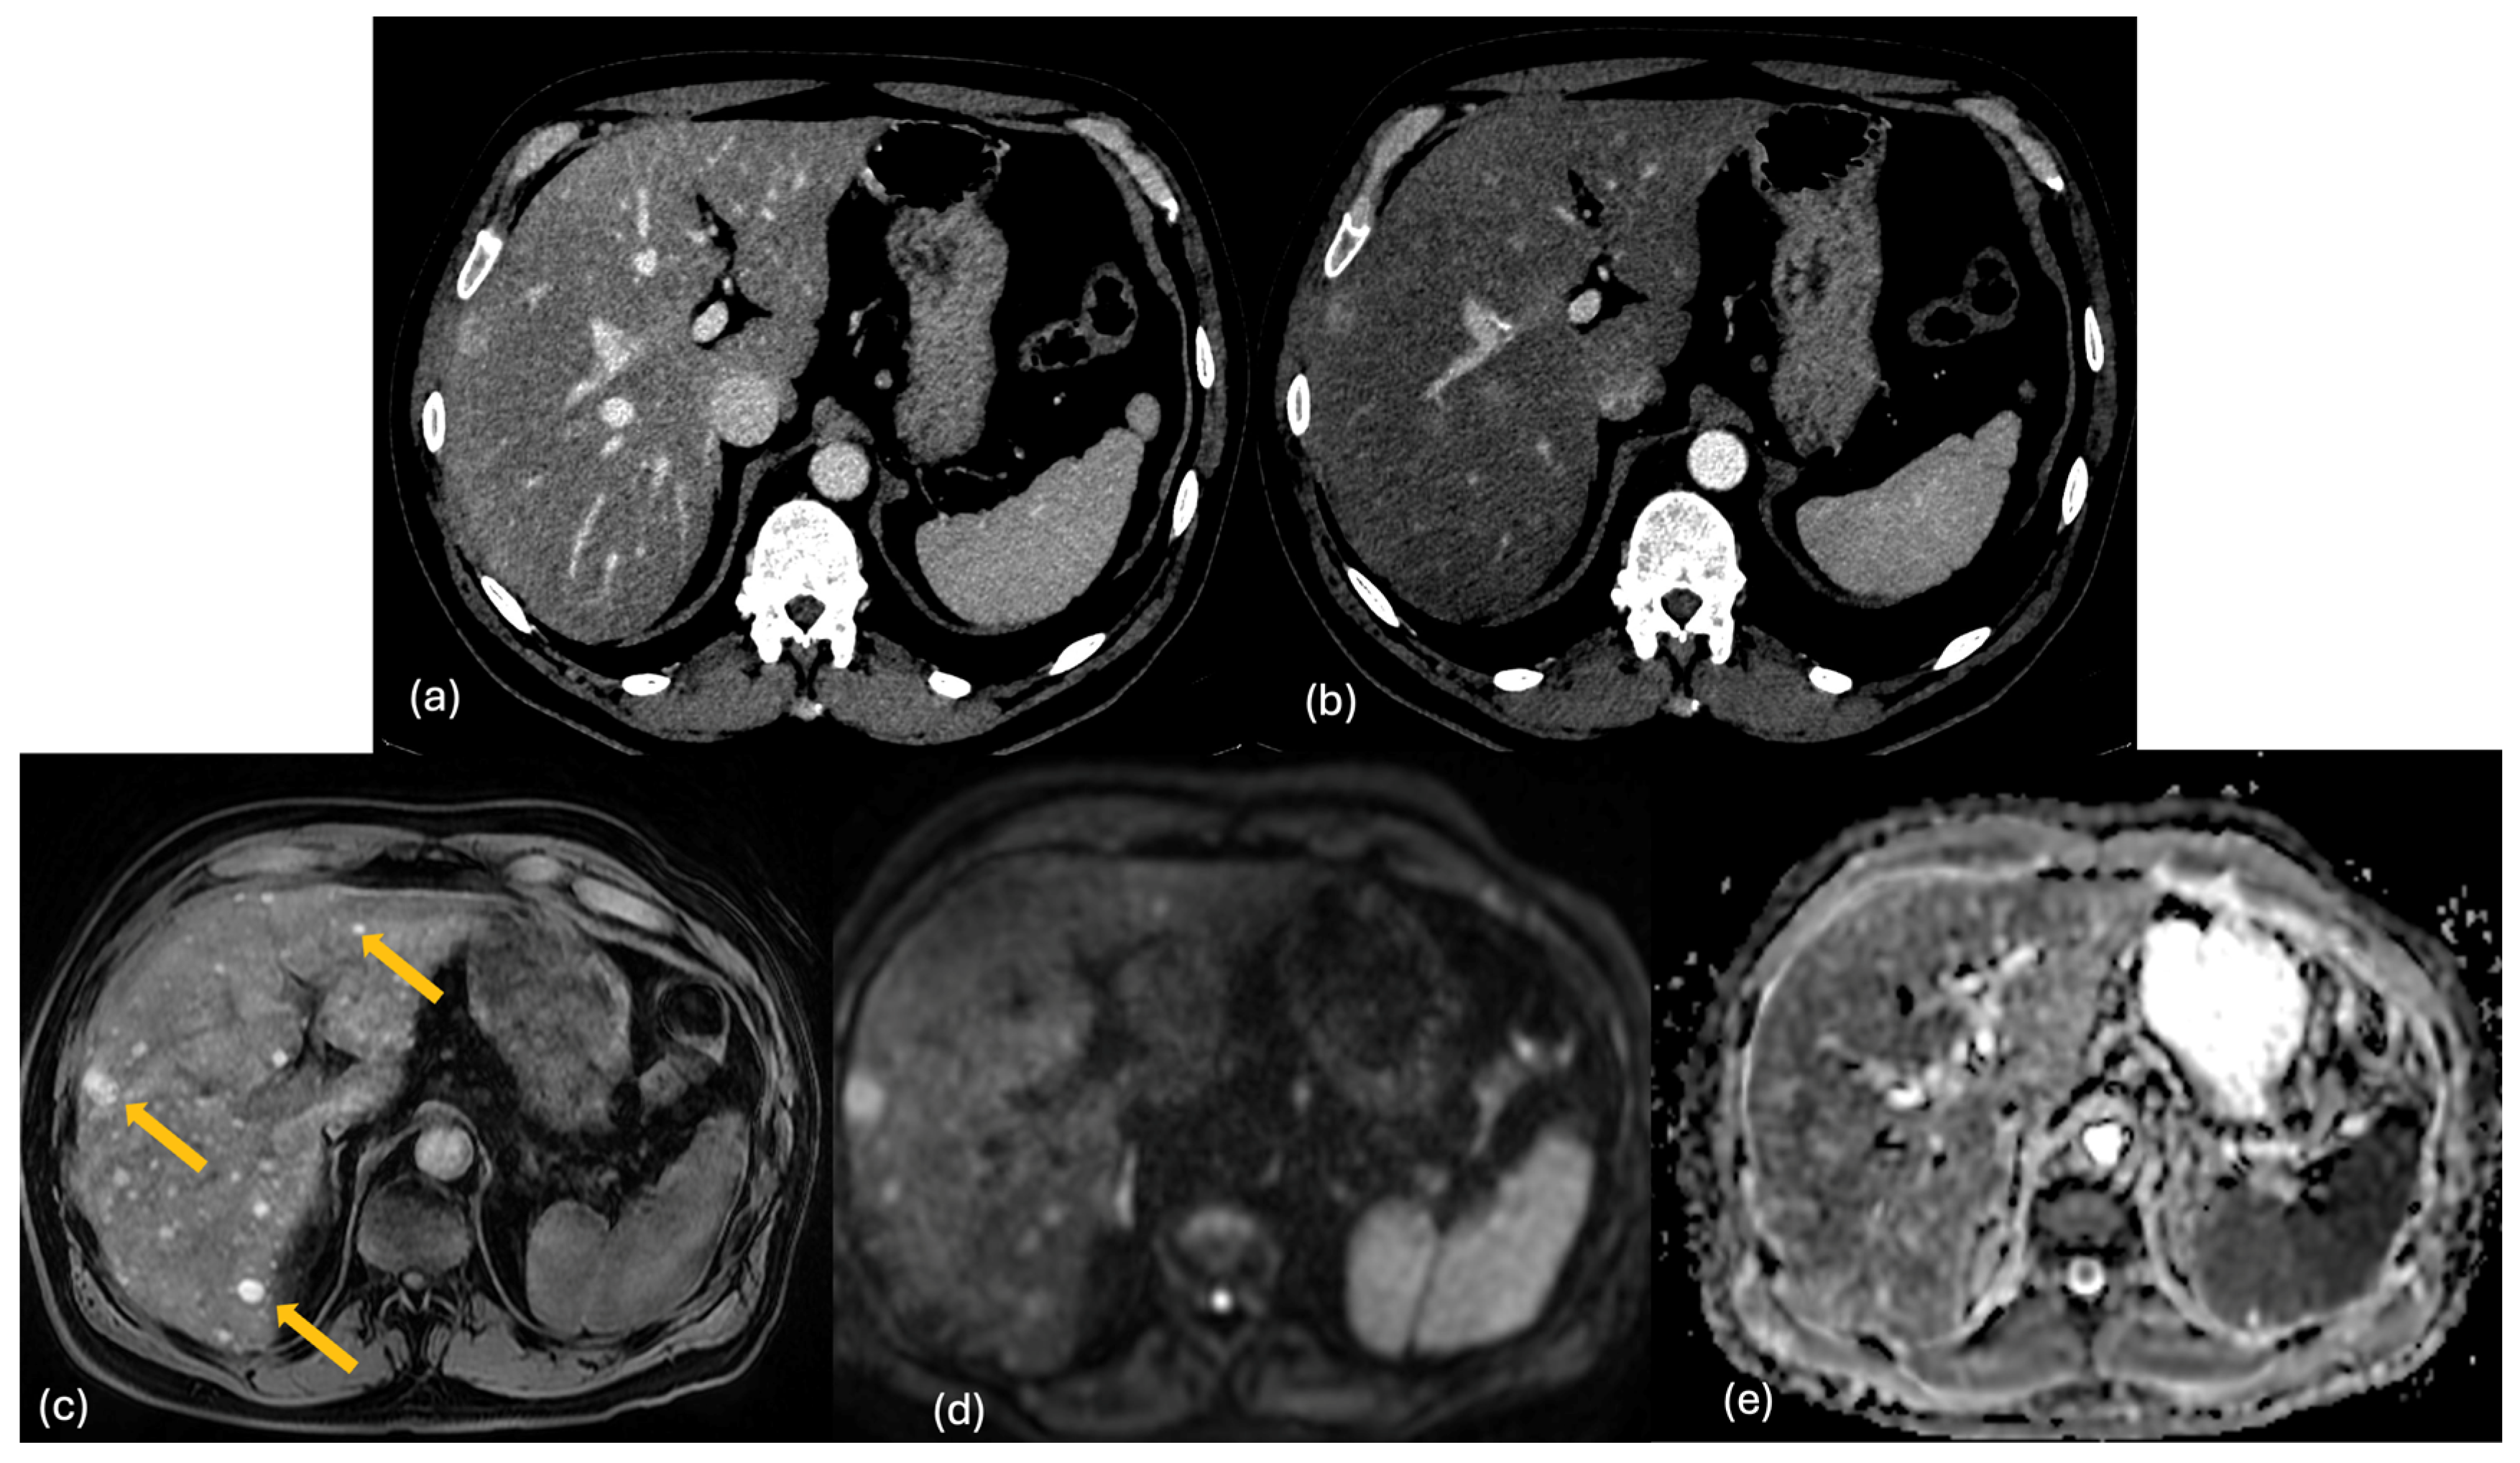

2.2. CT

2.3. MRI